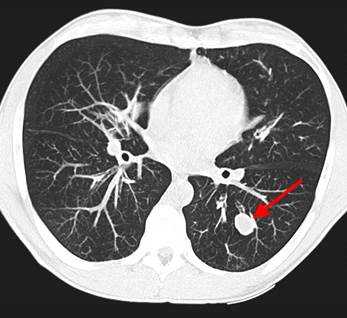

У пациента был выявлен раковый узел в 6 сегменте нижней доли слева. После резекции путем гистологического исследования верифицирован плоскоклеточный рак легкого. Томография в данном случае не дала типичную картину злокачественного новообразования.

2) Плоскоклеточный неороговевающий рак - часто встречающийся вариант - до 35% всех случаев образований легких. Характеризуется наилучшим прогнозом, редко метастазирует. Примерно в 65% развивается в одном из центральных бронхов и обуславливает картину ателектаза на КТ и рентгеновских снимках, в 35% развивается в периферических бронхах и выглядит как солидный единичный узел, часто с полостью распада в центре, похожий на абсцесс.

Типичный периферический рак легкого (аденокарцинома) на МСКТ. Справа в 6 сегменте легкого выявлен плотный мягкотканный узел со спикулами, деформирующий и подтягивающий к себе междолевую плевру.